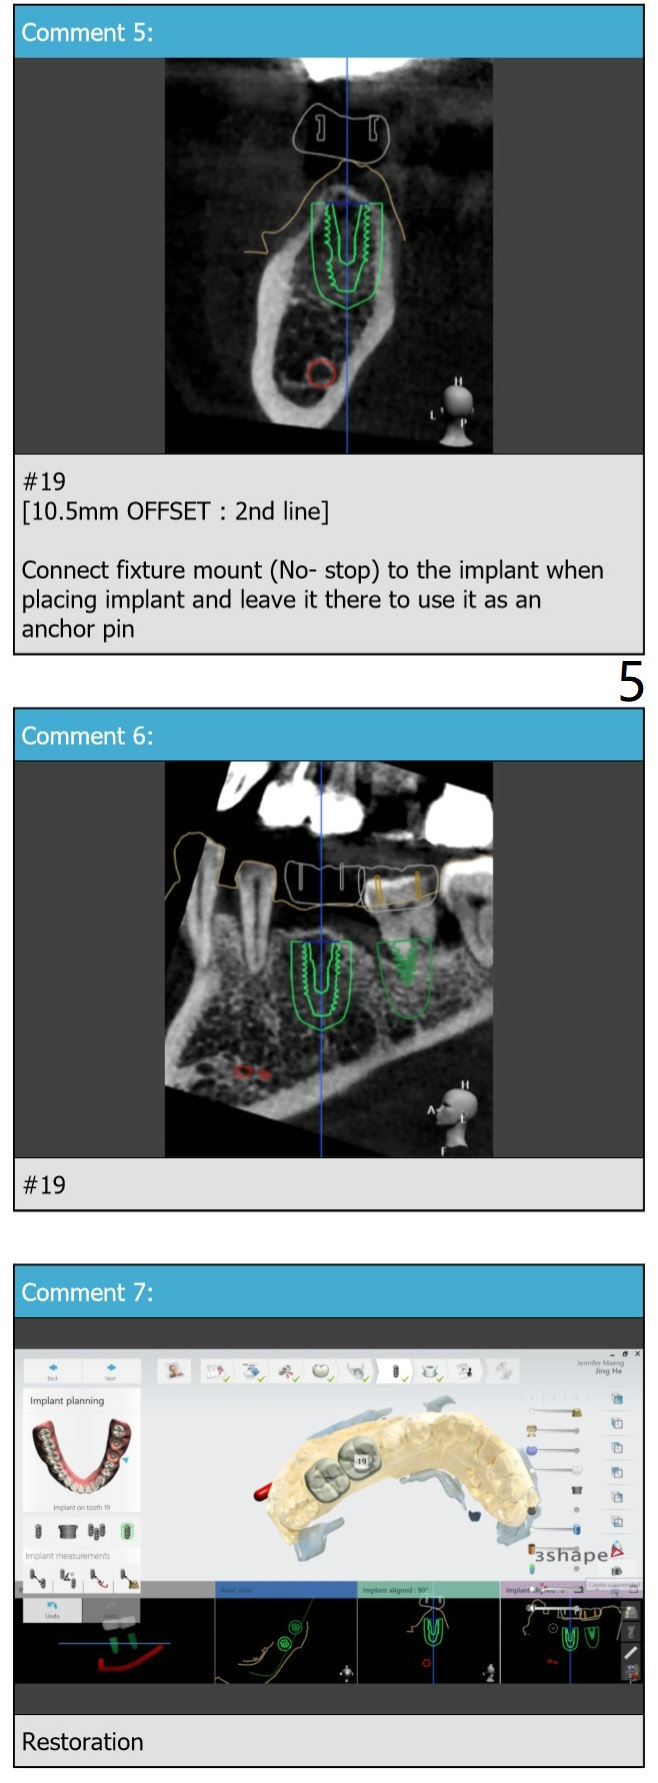

A 46-year-old woman

Molar Immediate Implant,

Prevent Molar Periimplantitis (Protocols,

Table),

Trajectory II,

No Deviation,

No Antibiotic